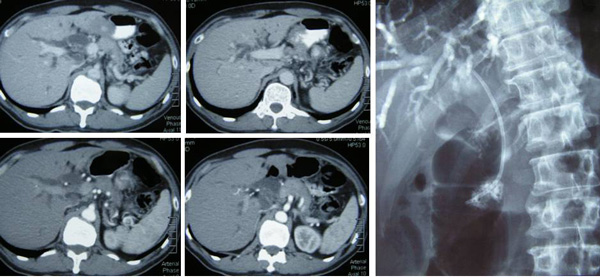

5. Lung cancer: Swensen describes the pseudodisease that emerges when computed tomography (CT scan) is used to screen for lung cancer. It detected 56 lung cancers over 4 years at the Mayo Clinic, but also a much larger number of uncalcified chest nodules, 98% of which were benign. He notes that wedge resection carries a 4% mortality rate, raising the prospect of patients’ dying on the operating table in the pursuit of pseudodisease.